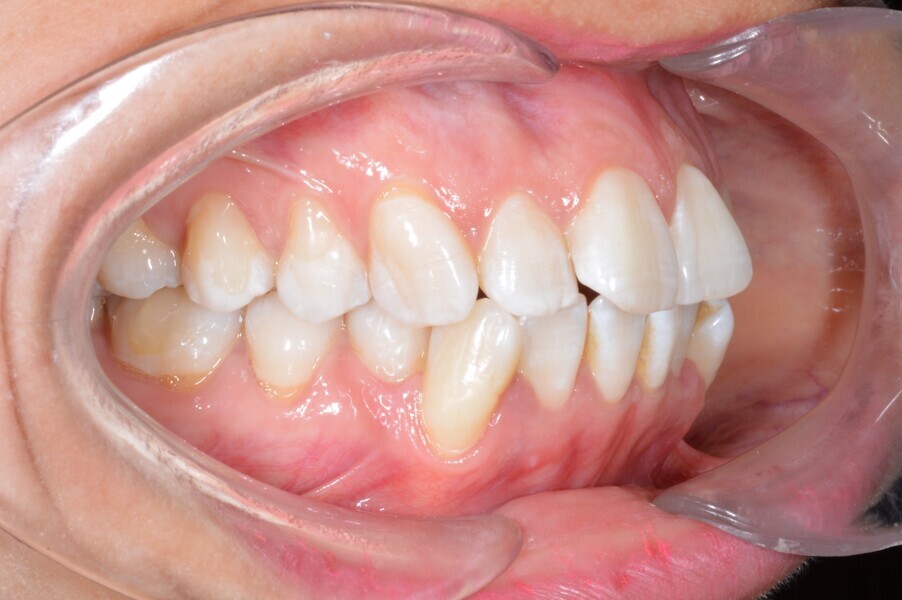

A 35-year-old female patient presented with crowding, muscle and joint pain, and headaches upon awakening. Examination found a skeletal Class I with crowding and bimaxillary protrusion. Facial examination showed a convex profile with protruded lips and a square face shape, intensified on smiling (Figs. 1–4). She reported bruxism, and bilateral masseteric hypertrophy was observed, but there was no alteration of the temporomandibular joints.

Before the aligner treatment began, the maxillary and mandibular second premolars were extracted to create space. With orthodontic treatment, distalisation of the anterior teeth was achieved by employing maximum mandibular anchorage and moderate maxillary anchorage (Figs. 5–7). At the end of the treatment, a stable bilateral Class I occlusion had been achieved, as well as normal inclination and retrusion of the anterior teeth, consequently improving the profile (Figs. 8–10).